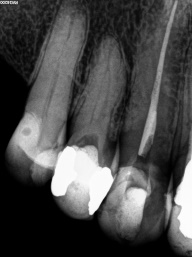

Em dentes de pessoas jovens, o canal é largo (amplo), com o decorrer do tempo e o envelhecimento natural, os canais vão diminuindo a sua luz ( o espaço interno ), tanto pela deposição continua de dentina, quanto por influências do meio externo, como trauma oclusal, caries, restaurações, e outros, com tudo isso, pode ocorrer desse espaço interno do dente ficar muito estreito (atresiado) ou até sumir por completo, ou seja completamente calcificado, quando chega nessa situação, é necessário o trabalho do endodontista para a localização dos canais calcificados e ou atresiados, limpeza e obturação com material indicado em cada caso.

Nos dias de hoje, existem técnicas e equipamentos que ajudam o profissional a conseguir o melhor resultados nessas situações, e uma delas é o uso do microscópio, que ajuda na localização das entradas dos canais atresiados e calcificados com maior precisão e segurança para o paciente.